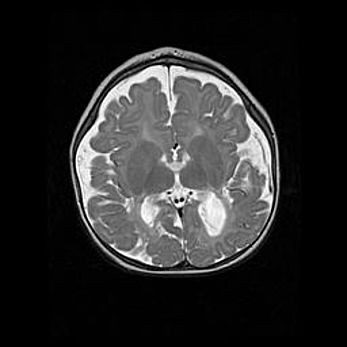

Лейкомаляция с кистозно-глиозной дегенерацией головного мозга.

Возраст: 2 месяца 25 дней

Вес: 6400 г

Окружность головы: 40 см

Срок гестации: 41 неделя

Лейкомаляцию относят к ишемически-гипоксическим повреждениям головного мозга, диагностируемым у новорожденных. При лейкомаляции в головном мозге обнаруживают очаги некроза, возникшие после тяжелой гипоксии и нарушения кровотока. В процессе морфогенеза очаги проходят три стадии: 1) развития некроза, 2) резорбции и 3) формирования глиозного рубца или кисты. Перивентрикулярная лейкомаляция (ПЛ) встречается примерно в 12% случаев среди новорожденных, обычно – у недоношенных детей, причем, частота ее зависит от массы, с которой младенец появился на свет. Наибольшее число малышей страдает лейкомаляцией, если масса при рождении 1500-2500 г.